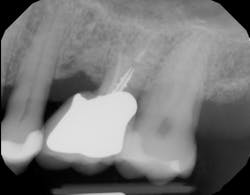

There is sufficient bone support around the remaining roots (at least 50% or more is needed) along with sufficient coronal tooth structure (figure 3).How does root amputation compare with other surgical procedures?

The prognosis is good for molar teeth treated with root amputation, provided case selection and treatment are performed properly. Fugazzottoreported 15-year cumulative success rates comparing molar root resection to molar implant placement, with survival rates of 96.8% for root-resected molars and 97.0% for molar implants.10 This study was done in private practice with proper oversight and case selection.Conclusion

Root amputation remains a viable treatment to save maxillary molars and can have long-term success rates equal to dental implant therapy (figures 9 and 10).Editor’s note: This article originally appeared in Perio-Implant Advisory, a chairside resource for dentists and hygienists that focuses on periodontal- and implant-related issues. Read more articles and subscribe to the newsletter.